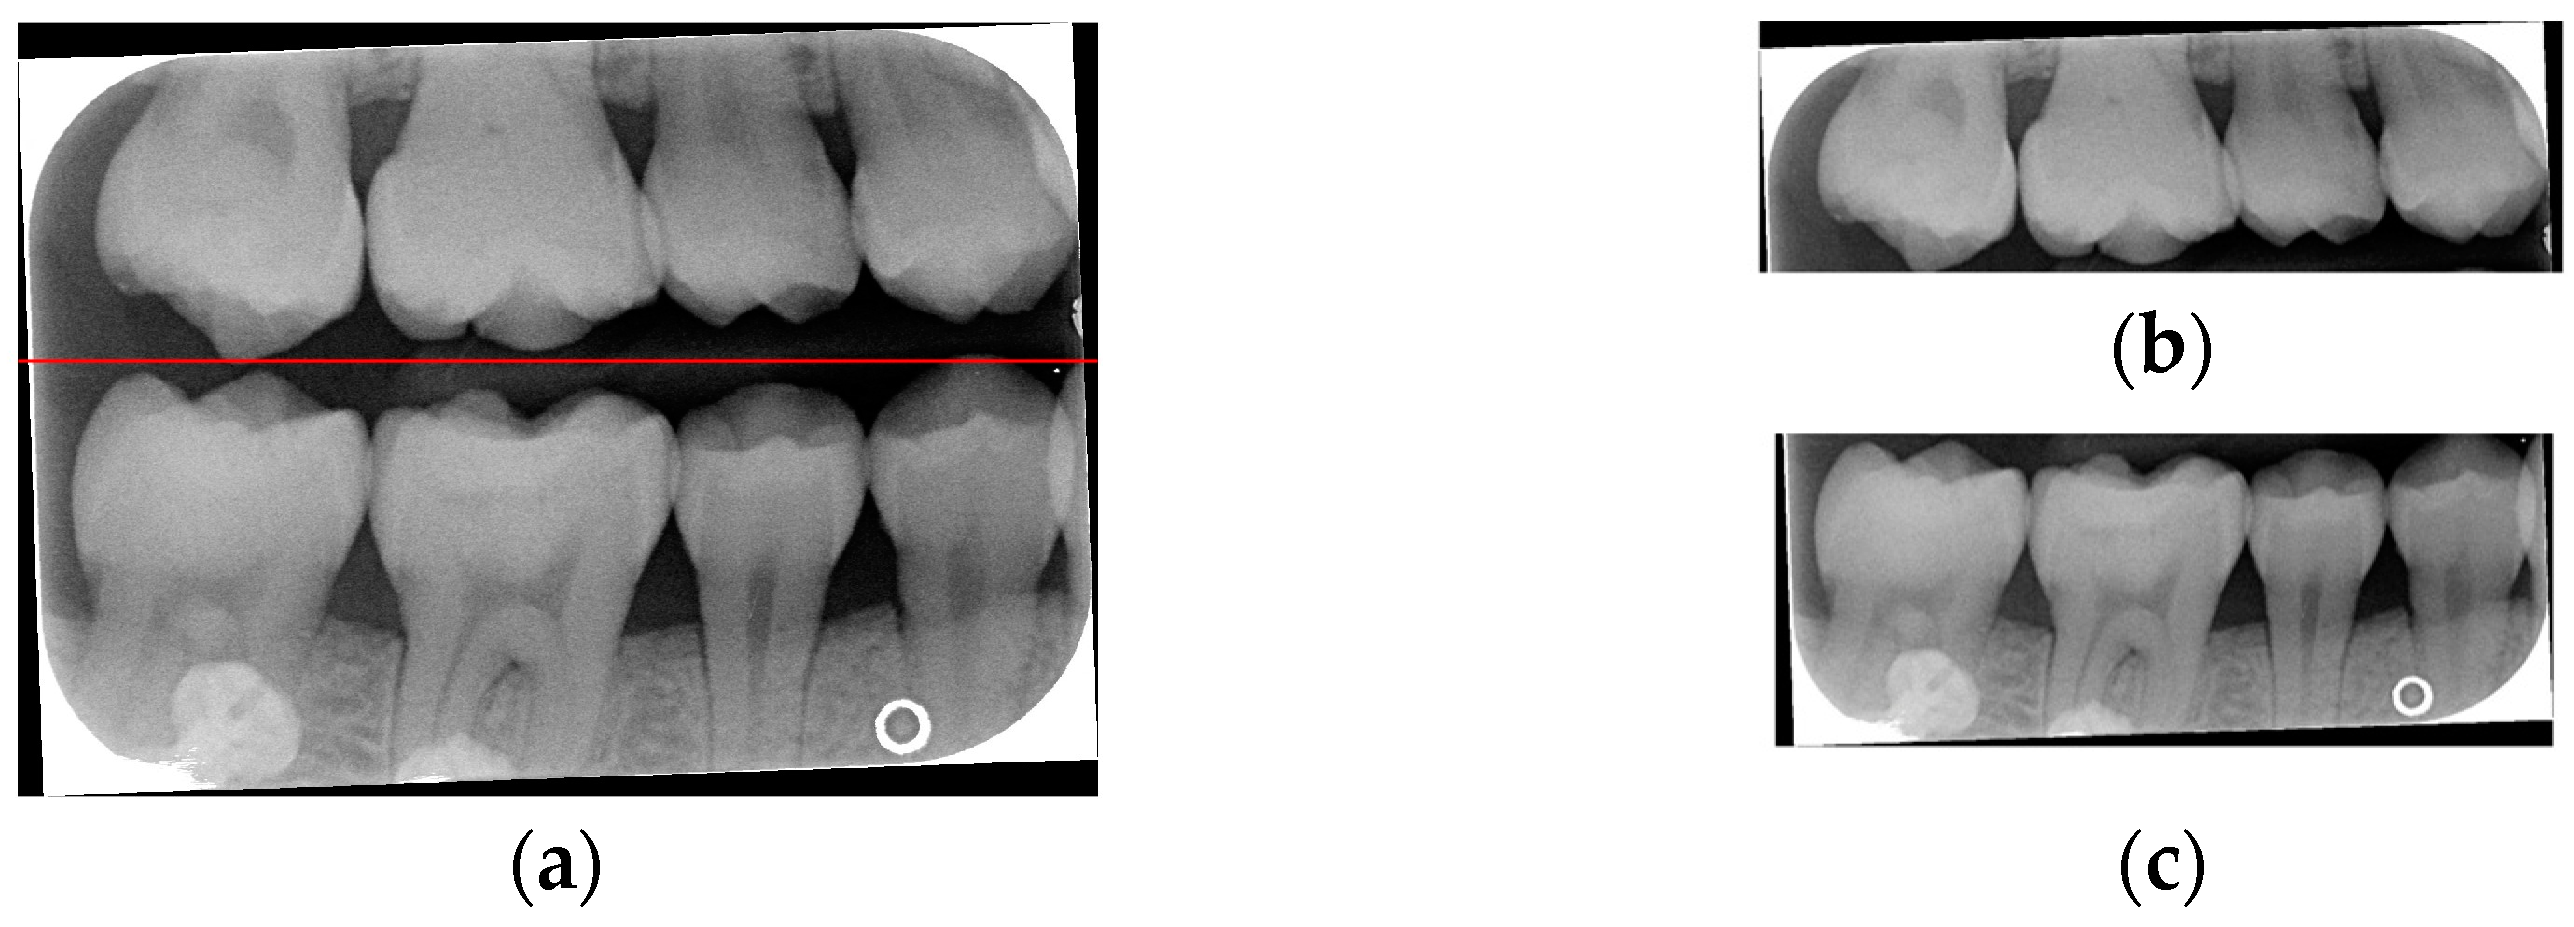

Due to angular issues in a BW, horizontal and vertical lines may not fully separate the teeth. This study addresses this by rotating and binarizing images multiple times to enhance the contrast between teeth and gaps. High-contrast images allow for accurate identification of tooth gaps through pixel horizontal projection as shown in Figure 4a. The image is divided horizontally into three parts, masking the upper and lower sections to focus on the middle, like the upper and lower sides of the red box in Figure 4b are masked. The valleys of the projection line in this region are identified as the x-minimum value, and the y-coordinate of the valley represents the vertical height separating the upper and lower rows of teeth after rotation. Additionally, during each rotation, a projection is made to identify the trough position in the middle of the image. The trough values (x-minimum) at each angle are compared to determining the optimal rotation angle for horizontal segmentation. Initially, the image is rotated within a range of plus or minus 15 degrees, in increments of 5 degrees. By comparing the trough values at each angle, the most suitable rotation angle for horizontal cutting is identified, as shown in Figure 4b.

Figure 4.

Horizontal projection of the rotated image. (a) BW rotated +5 degrees; (b) BW rotated +10 degrees.

According to Table 1. After performing small-angle rotations and comparing the trough values at each angle, it was determined that the lowest trough value (x = 36) occurs at a rotation of 11 degrees, which is lower than the trough value (x = 40) obtained at the initial rotation of 10 degrees. Therefore, it can be concluded that a positive 11 degrees is the most suitable rotation angle for this BW, which is more favorable for subsequent horizontal segmentation. If a smaller rotation angle is used from the beginning to find a suitable angle, multiple calculations will be required within the same range of angles. However, by gradually rotating the image in two steps, one large angle (5 degrees) and one small angle (1 degree) to obtain the most suitable rotation angle, we achieve the same result and find out the suitable angle more quickly. After rotating the image of each BW to a suitable angle, the height of the trough (y-value) is found. The height of the plumb coordinates of the troughs are found and the horizontal line separating the upper and lower jaws is plotted using the height of these coordinates. This allows the entire BW to be divided into upper and lower rows of teeth; the specific segmentation result is shown in Figure 5.

Figure 5.

Segmentation of the upper and lower rows of teeth of the BW. (a) Horizontal line drawing of the lowest pixel coordinates. (b) Upper row of teeth. (c) Lower row of teeth.